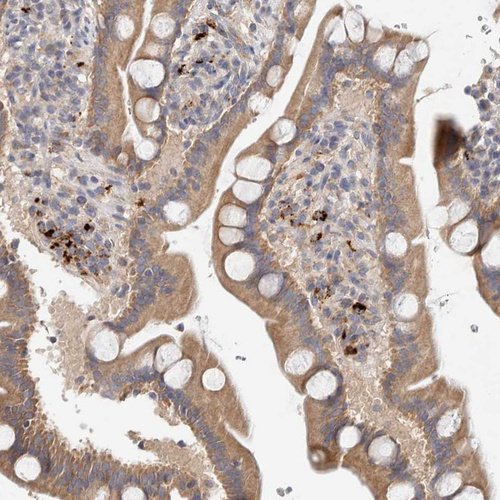

Immunohistochemical staining of human duodenum shows moderate cytoplasmic-membranous positivity in glandular cells.